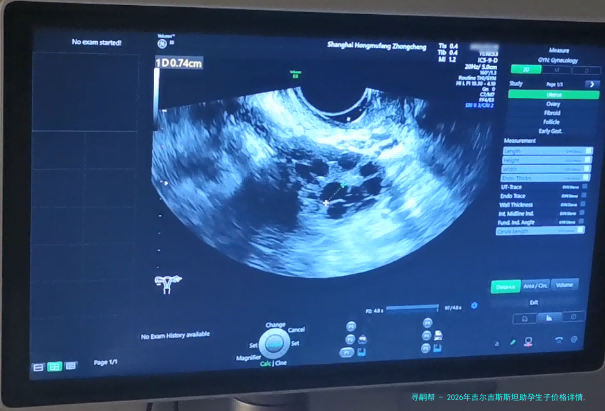

促排卵手术费用:医生会在B超引导下,通过阴道穿刺取出卵子。促排卵手术费用大概在800美圆至1500美金之间。